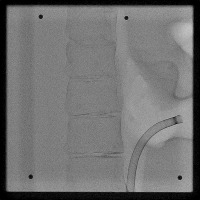

Healthcare Monitoring: "Cath" can be used in a real-time monitoring system within healthcare facilities. It can identify the position and type of a catheter tip in an x-ray, greatly helping healthcare professionals to assess the situation of patients having a lumbar puncture or spinal catheter implantation.

Medical Diagnosis: "Cath" can be used in the diagnosis of possible complications associated with catheter placements. Early detection of catheter displacement can prevent further complications.